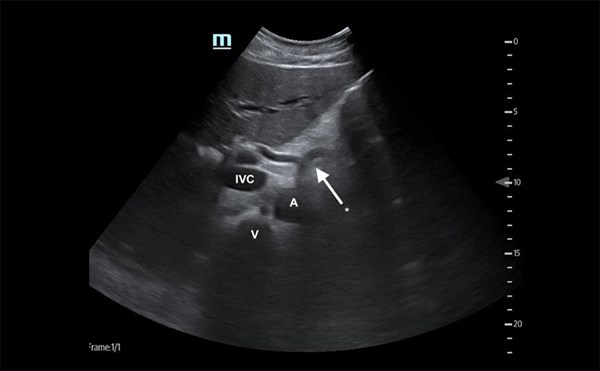

Advanced ultrasound can enhance the diagnosis of organ injury, viable tumor, and vascular pathologies at bedside.